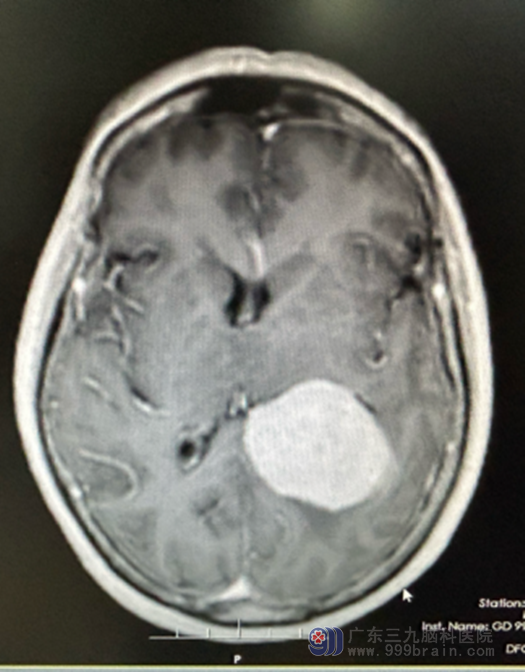

七月中旬,来自广东省湛江市的张女士,主诉近半年来无明显诱因出现记忆减退,当时未引起重视,近2个月来又出现言语迟缓,伴有四肢无力,但无明显恶心呕吐、四肢抽搐等不适,曾到当地医院就诊,查头颅MR示“左侧脑室三角区占位性病变,考虑脑膜瘤”,患者及其家属为进一步检查及治疗遂来我院就诊,我院欧阳辉教授将其收入神经外十科住院。入院后完善相关检查,3.0TMR结果提示:1..左侧侧脑室、三角区占位性病变,考虑脑膜瘤

检查意见:左侧侧脑室三角区病变血供丰富。